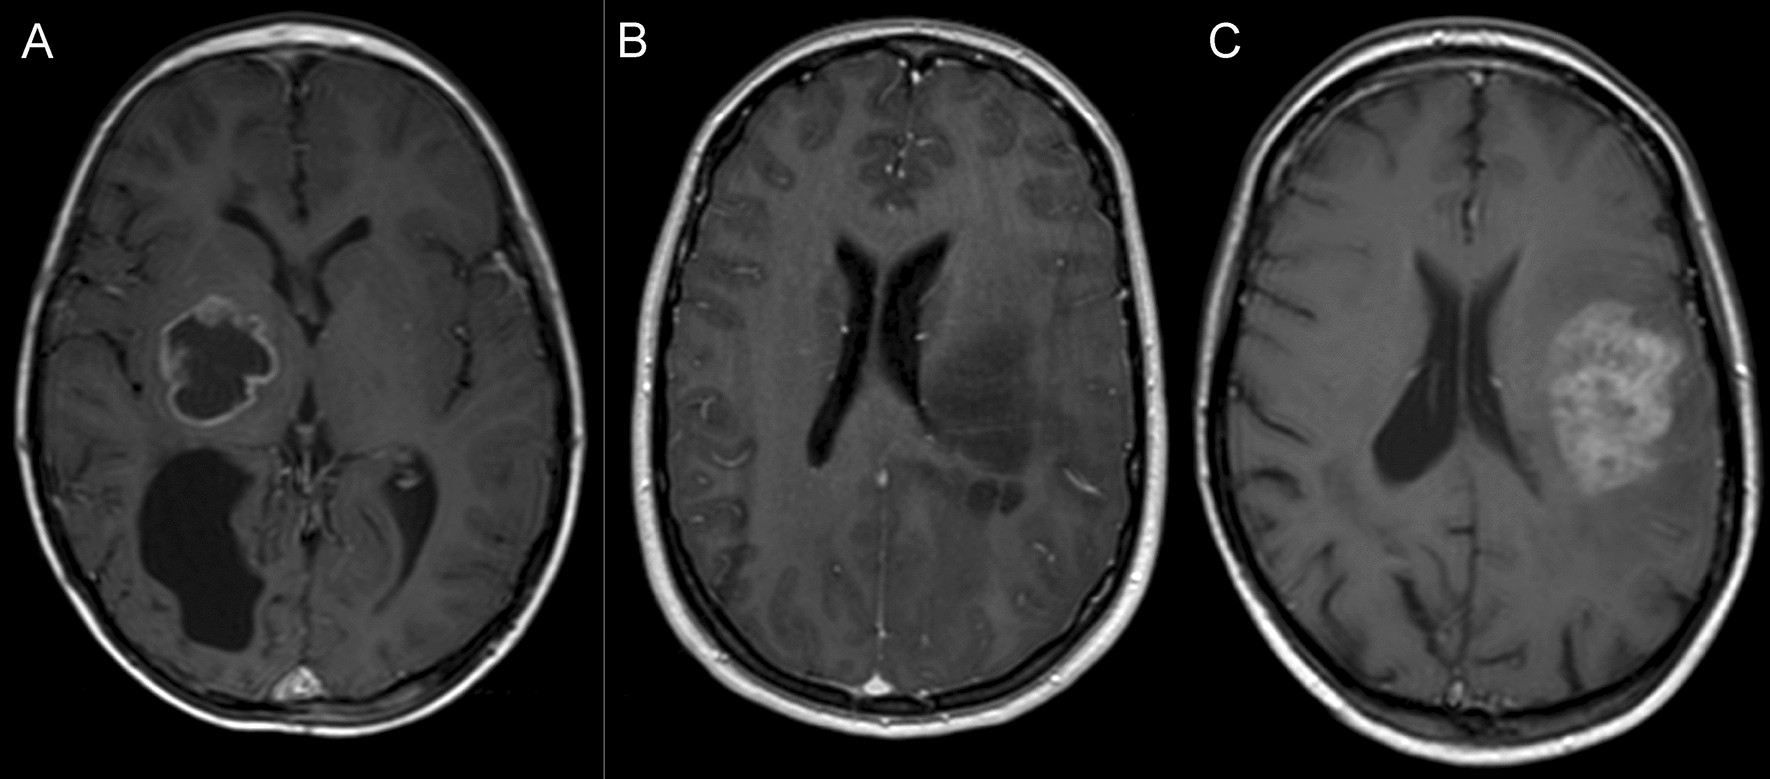

Figure 2

From: Clinical and molecular study of radiation-induced gliomas

Radiological characteristics of RIG. Examples of radiological subgroups of RIG according to the character of contrast enhancement: (A) arcuate pattern enhancement—RIG2, (B) no enhancement—RIG6, (C) diffuse enhancement—RIG11.